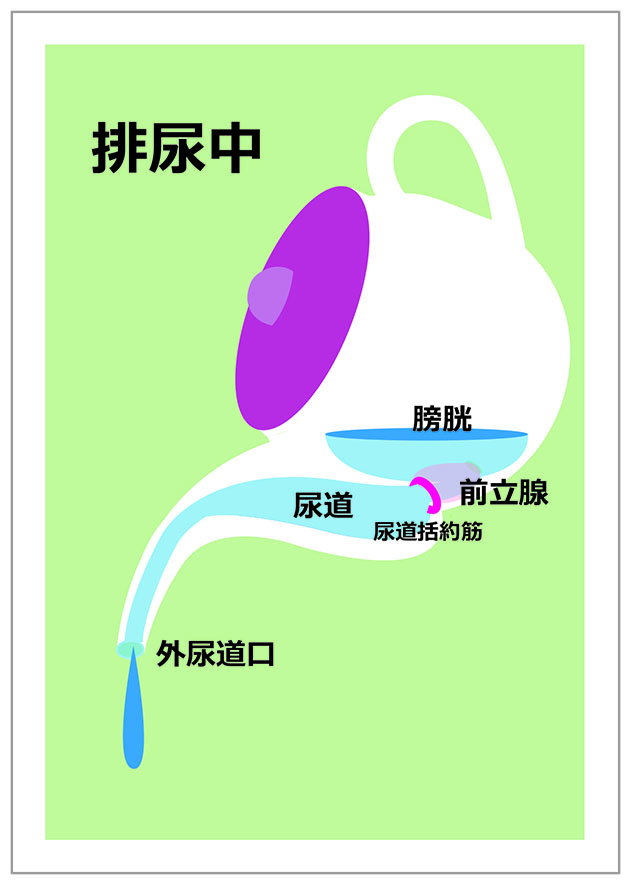

前立腺炎の場合、一般的には会陰部(肛門の前)の鈍痛、 睾丸の鈍痛、排尿痛があげられます。 そして、前立腺炎では多くの場合、この会陰部に痛みが生じます。 会陰部の痛み 急性前立腺炎の場合 急性前立腺炎の場合は、高熱と会陰部痛をともなうため、 男性 会陰部にしこり person 30代/男性 前も相談させて頂きました。 だんなが睾丸のすぐ下から肛門の間にしこりを発見しました。 去年には肛門周囲膿瘍で入院したこともあり、診察を受けに行きましたが、経過は大丈夫で、しこりについては1919 男性 男性の尿道は長く、外尿道口から入った細菌は、膀胱に達する前に排尿によって流されることが多い。前立腺からの分泌液には、細菌の侵入を防ぐ働きがある。 女性 女性は、男性に比べて、尿道が短い上、肛門や膣前庭部と外尿道口が近いので、その分、細菌が膀胱の中に入りやすい。

男の尿トラブルの主犯は前立腺肥大 ちょい漏れは会陰部指圧で解決 尿のトラブル 自力で解決 日経gooday グッデイ

尿が垂れる その対策 男性編 こだいら泌尿器科

おしっこトラブル 50代の5人に1人が悩む不快なチョイもれ 排尿後尿滴下 とは ケンカツ

尿が垂れる その対策 男性編 こだいら泌尿器科

悩ましい 残尿 に秘策はあるか ライフリー ユニ チャーム

尿漏れ男の対策 出終わったと思った後に出るときにする3つのこと 40代の中年男の情報マガジン